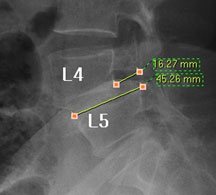

모커리한방병원 위 뼈가 50%정도 밀려나간 모습 이미지

척추전방전위증은 척추 주변, 특히 척추 후방에 있는 후관절 주변의 근육과 인대 그리고 후관절 자체가 퇴행되어 척추 뼈를 제대로 붙잡아 주지 못해 위아래 척추 뼈가 앞뒤로 밀려 나가면서 발생하는 척추질환을 말합니다.